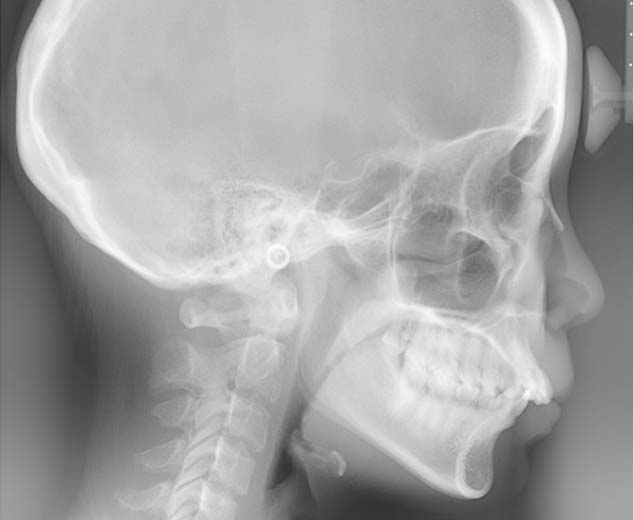

初診検査

約45分から1時間ほど

初診相談後、治療をご希望される場合は、初診検査を実施します。この検査で、患者様の現在の口腔内の状態を確認します。

顔貌・口腔内写真の撮影

レントゲン撮影

歯型の模型採取

初診検査の結果は、約2~3週間後にお伝えします。その際、診断と治療方針を決定します。